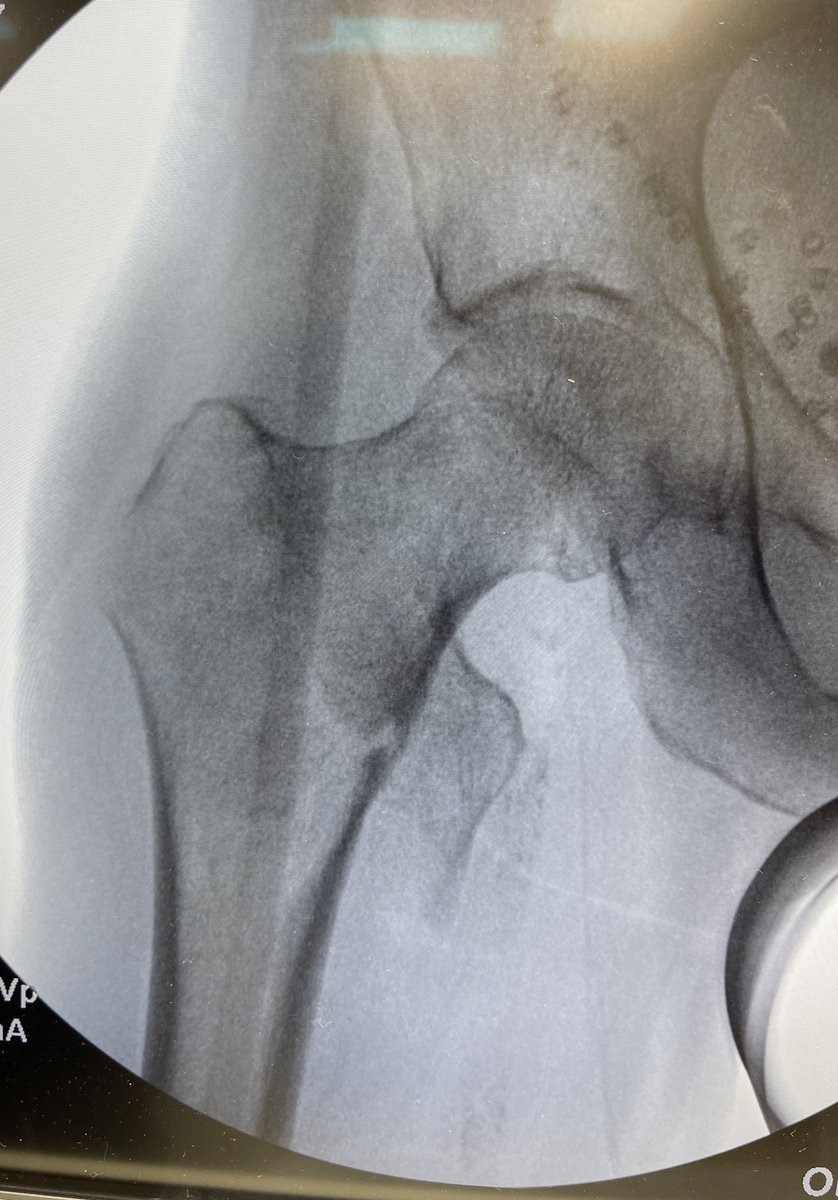

45y male, what is your plan of reduction and fixation? P.S: don't have a CT.@DrBhavinJadav @FractureDoc @InvictaOrtho #orthotwitter @

45y male, what is your plan of reduction and fixation?

P.S: don't have a CT.@DrBhavinJadav @FractureDoc @InvictaOrtho #orthotwitter